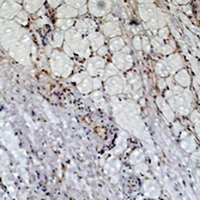

IHC (Immunohiostchemistry)

(Immunohistochemical analysis of Peroxiredoxin 1 staining in human Heptocancer formalin fixed paraffin embedded tissue section. The section was pre-treated using heat mediated antigen retrieval with sodium citrate buffer (pH 6.0). The section was then incubated with the antibody at room temperature and detected using an HRP conjugated compact polymer system. DAB was used as the chromogen. The section was then counterstained with haematoxylin and mounted with DPX.)